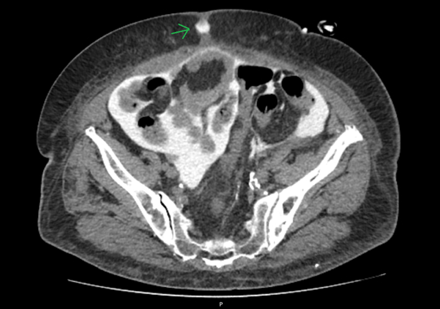

To assess for a possible peri-catheter leak and rule out a catheter fracture, a computed tomography (CT) scan was performed with contrast infusion into the peritoneal cavity (Figure 2 and Figure 3). The protocol included a standard non-contrast CT scan followed by a 2 h dwell of 1.36% glucose dialysate to which 100 ml of contrast was added, comprising a total of 2 liters of infused fluid.

Figure 3.

A second CT scan was performed afterward. Imaging showed dialysate drainage through the midline in the periumbilical region, where there was also significant adipose tissue densification. Intraperitoneal pressure was not measured at this time.

A small break in the catheter tubing resulting in drainage through the closest weak point on the abdominal wall (in this case, the linea alba) was considered to be the most probable cause, and the patient was referred for elective corrective surgery.